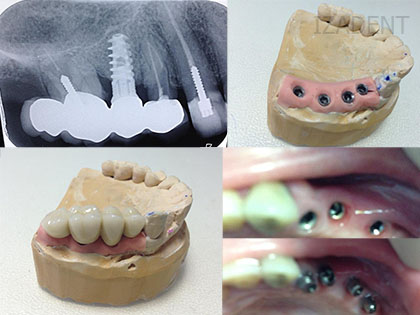

Implanturi